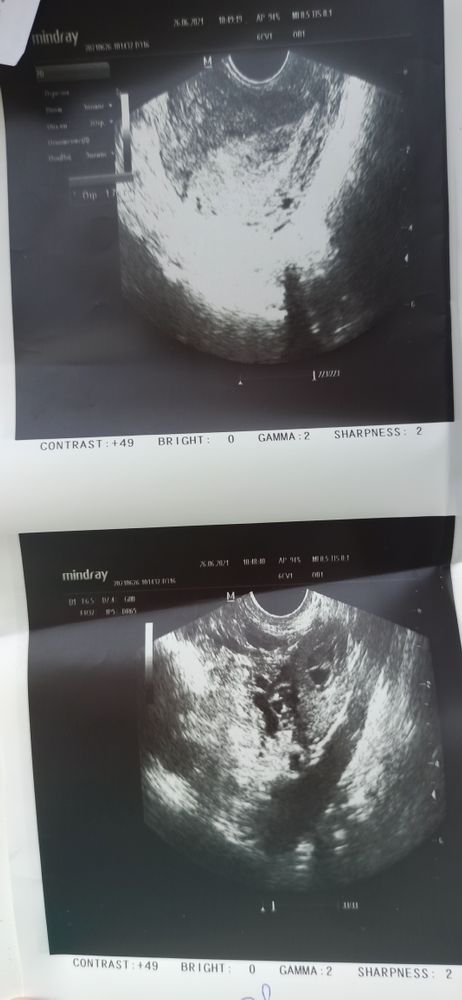

Узи при задержке 10 дней

Здравствуйте, есть беременность?

Узи делали трансвагинально